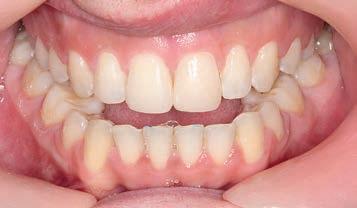

Figs. 1a–h: Initial situation: patient’s facial view (a-c); intraoral view (d-f); cephalometric X-ray (g); pantomograph X-ray (h).

A female, age 23 years, 5 months, presented for treatment exhibiting a moderate Class III malocclusion with negative overjet, proclined lower lip with flat supramentale sulcus, open bite and crowding in the lower arch. The treatment plan was to distalise the lower dentition into a Class I occlusion (Sagittal First) using the Carriere Motion CL III Appliance, then generate space to alleviate the lower arch crowding and close the bite, utilising light-force archwires in a passive, self-ligating system. While tongue trainers would be bonded in conjunction with the fixed appliances later in treatment, the patient would also engage in tongue training exercises to correct her improper

3 months: Class I platform achieved

By 3 months, the sagittal aspect had corrected to the occlusal lock of the Class I platform (Sagittal First) with the counter clockwise movement of the lower occlusal plane. Note that the lower canines had extruded slightly. Some extrusion of canines is a positive sign of the counter clockwise rotation of the lower posterior occlusal plane that fosters a better positioning of the mandible in relation to the maxilla—a direct effect of the appliance. The Motion appliance was removed and tongue trainers were bonded to the lingual aspects of the lower incisors to continue to train the tongue to position itself properly in the oral cavity, specifically during swallowing and mastication. Concurrent with the tongue trainers, Carriere SLX .022 PSL brackets were bonded.

3 months of sagittal correction, the occlusal lock of the Class I platform had been accomplished (Sagittal First) and the case was ready to progress to the next stage. The Motion appliance was removed. While in this case, it would have been easy to finish the case with Invisalign, the patient chose fixed appliances so Carriere SLX .022 PSL brackets were bonded.

11 months: Sagittal and fixed appliance treatment complete

With 3 months of sagittal treatment and 8 months of fixed appliance treatment, the case finished to a harmonic occlusal and facial result. The result exhibits an excellent repositioning of the mandible held in position by the occlusal lock of the Class I platform (intercuspation of the molars, premolars and canines). The mandibular repositioning

was obviously not a result of growth in a 27-yearold woman, but the result of balancing the structures of the temporomandibular joint, reposturing the mandible in the temporomandibular space. Prior to treatment, she could not protrude her mandible even to position her lower anterior teeth into the lingual aspect her upper anterior teeth. For this patient, the mandibular reposturing created a dramatic, positive change in her facial profile to create a beautiful symmetry. Figures 16 to 18 offer illustrations of this reposturing. An indication of the extent of this movement is the fact that after treatment, the patient was able to protrude her mandible beyond her maxilla.